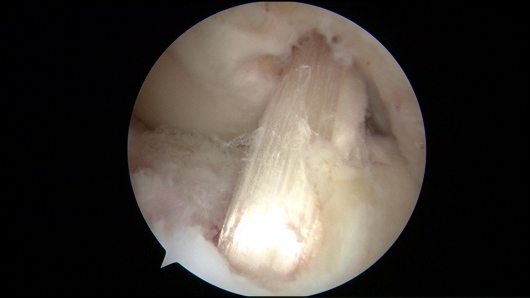

Además de la cirugía de reemplazo articular, me especializo en procedimientos de preservación articular y artroscopia de cadera y rodilla, buscando siempre retrasar o evitar la cirugía de reemplazo articular cuando es posible.

- Artroscopia

- Lesión del Ligamento Cruzado Anterior (LCA)

- Desgarre de meniscos

- Desgarres del Labrum de la Cadera

Cordial saludo, el Betaduo es un corticoide que eventualmente disminuirá tu dolor en la rodilla si es inyectado adecuadamente, sin embargo esto será temporal si lo que hay es una ruptura o lesión de la estructura, lo que usualmente amerita un manejo de la lesión por medio de una artroscopia de la rodilla. No te recomiendo esta inyección sin una adecuada valoración médica.